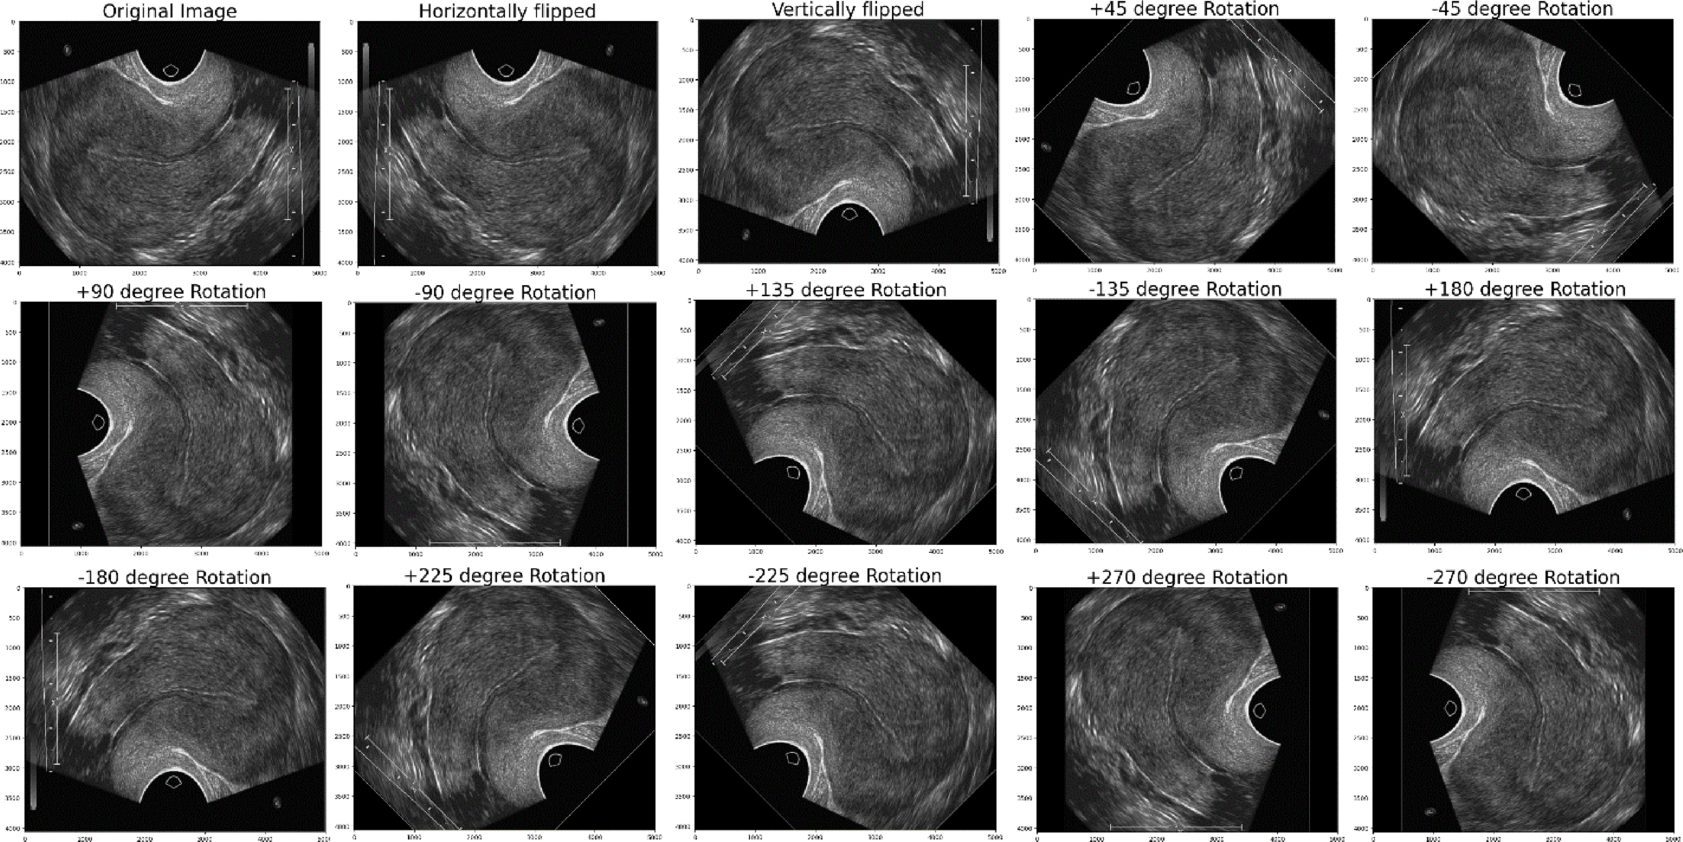

Fig. 12

Results of Normal healthy ultrasound Data Augmentation Images.